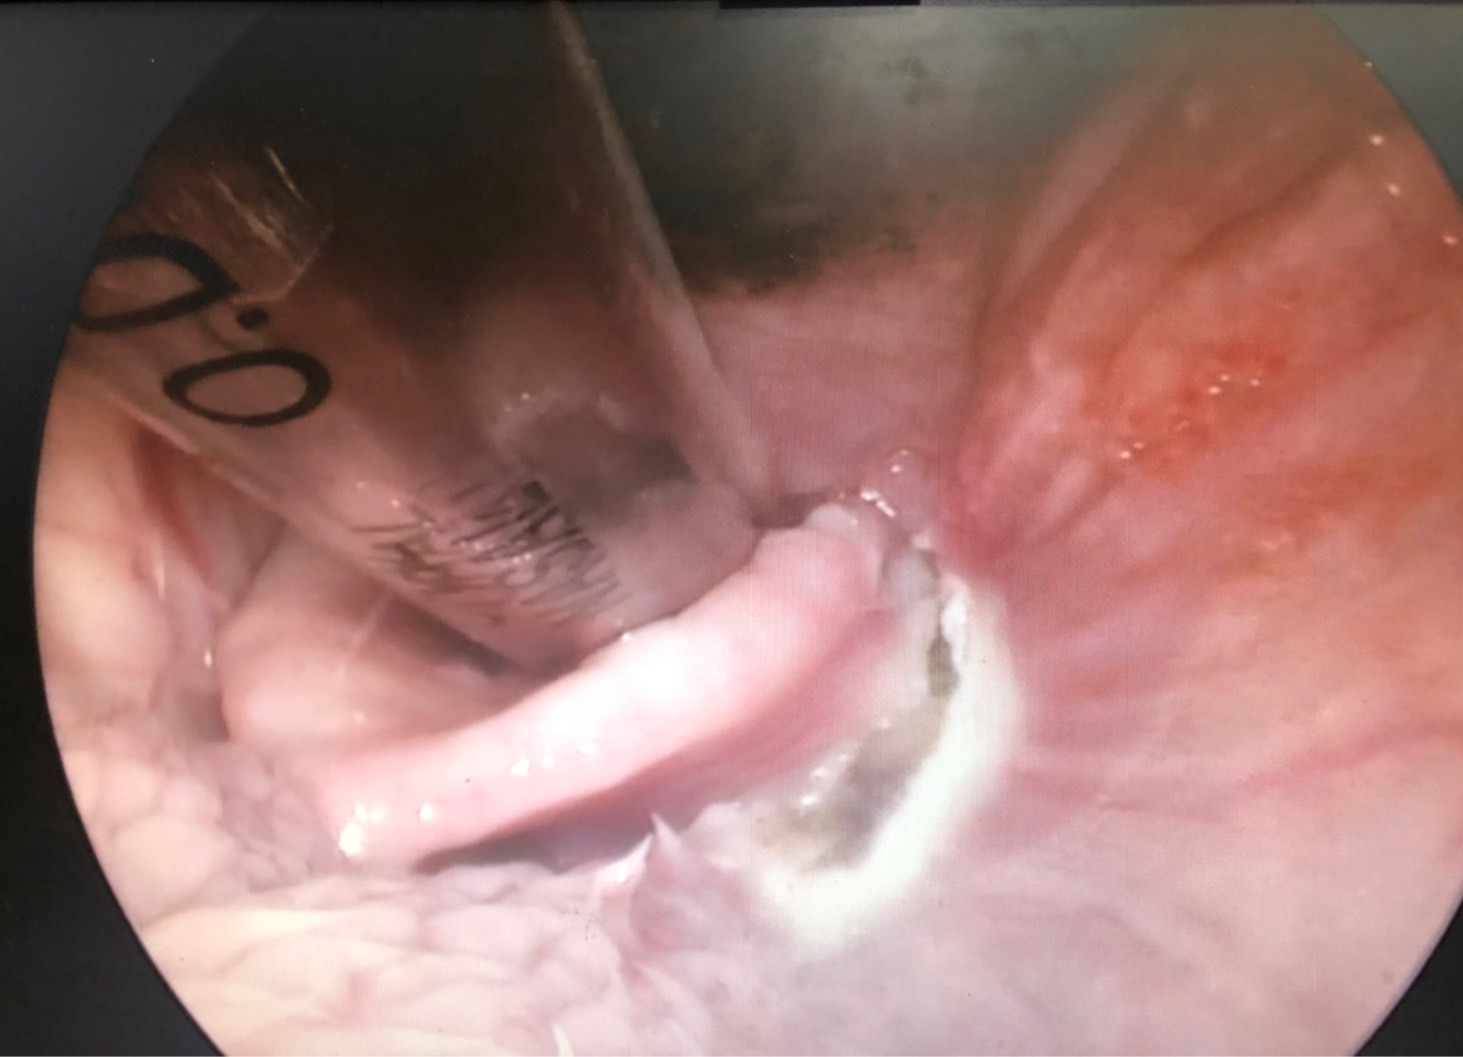

初步懷疑呼吸道阻塞,安排電腦斷層掃描/內視鏡探查手術,精準定位病灶團塊的範圍,利用內視鏡輔助套環套住團塊後經電燒將可見到範圍盡量切除乾淨。

同時將切除的團塊做病理切片。術後三個月到現在沒有症狀也沒有復發。

病理報告為嚴重、慢性活躍性、漿細胞及化膿性喉炎,伴隨肉芽組織生成及局部上皮細胞異型性,會厭旁團塊